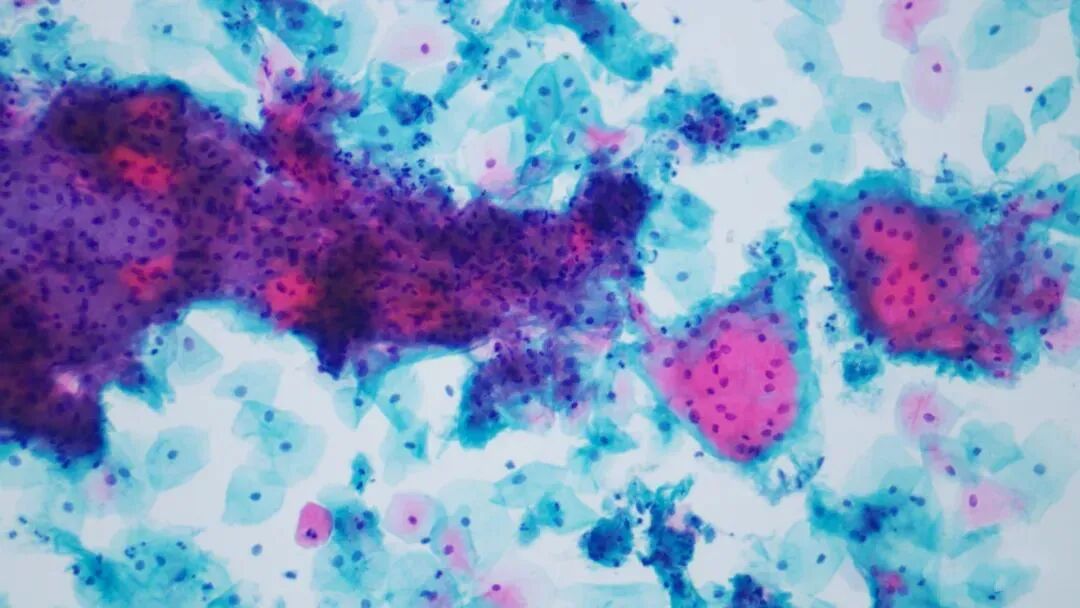

我们先来一例宫颈液基大家赏析:

最后回到开头病例,是个滴虫病例,再看一下

典型滴虫特征:

两张视野中央的滴虫,梨形淡蓝色,脊状核,隐约的鞭毛;(大家下载图片放大看)

周围鳞状上皮核反应性增大,核周空晕,胞浆双染,胞浆空泡,散在中性粒细胞簇。

其实这例当时因为一些核大而纠结于要不要发ASCUS,所以看了半天才发现原来是个滴虫。